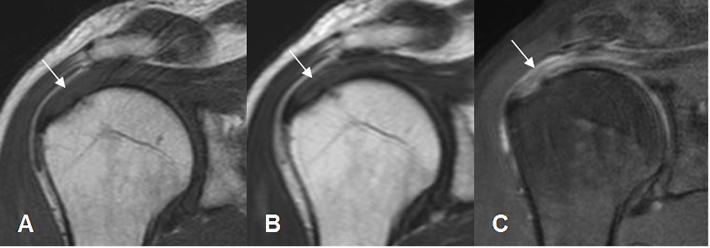

Fig 19. Tendinitis del supraespinoso.

A: RM coronal en T1. Aumento en la señal del tendón supraespinoso.

B: RM coronal en T2 y C: RM coronal en STIR. El supraespinoso es hiperintenso, irregular y rodeado por líquido, por tendinitis